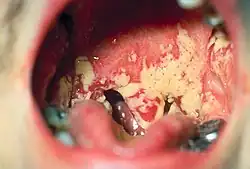

Des spirochètes et bacilles fusiformes font partie de la flore commensale (normale) de la bouche. En cas de lésion des muqueuses de la cavité buccale, et sous l'effet de facteurs favorisants tels que la plaque dentaire, ces bactéries peuvent devenir pathogènes et causer des maladies infectieuses des tissus situés à ce niveau :

- infections parodontales sévères : gingivite ulcéro-nécrotique (GUN) aiguë et parodontite ulcéro-nécrotique (PUN) aiguë

- angine de Vincent (avec une membrane d'aspect particulier recouvrant l'amygdale)